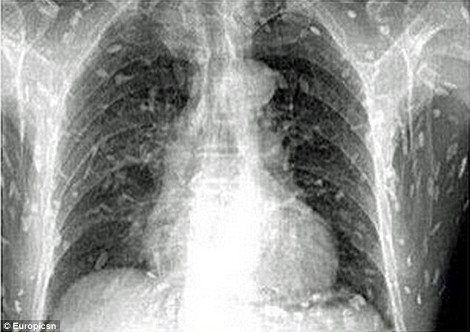

Είναι το πιο ακριβό και κατά πολλούς το πιο νόστιμο σημείο του σούσι. Ωστόσο η αγάπη ενός άνδρα για το σασίμι παραλίγο να αποβεί μοιραία, αφού εξέθεσε το σώμα του σε...σκουλήκια. Συγκεκριμένα, σύμφωνα με τη Daily Mail, ένας άνδρας επισκέφθηκε τον γιατρό του στην επαρχία Guangdong της ανατολικής Κίνας, έπειτα από στομαχικούς πόνους κι έντονη φαγούρα. Προς μεγάλη του έκπληξη ανακάλυψε ότι στις ακτινογραφίες στις οποίες είχε υποβληθεί, διακρίνονταν εκατοντάδες σκουλήκια να «αλωνίζουν» στο έντερό του και σε άλλα ζωτικά όργανα. Αιτία, σύμφωνα με τους γιατρούς, δεν είναι άλλη από την κατανάλωση χαλασμένου ωμού ψαριού. Ο ασθενής εισήχθη στο νοσοκομείο για θεραπεία. Την ίδια ώρα, έρευνες έχουν δείξει ότι η ολοένα αυξανόμενη προτίμηση σε παγκόσμιο επίπεδο των καταναλωτών στο σούσι, έχει προκαλέσει και την αύξηση των κρουσμάτων σοβαρής δηλητηρίασης και άλλων παρασιτικών μολύνσεων. Συνήθως, εκείνοι που προσβάλλονται συχνότερα είναι οι καταναλωτές που προτιμούν τον ωμό σολομό.